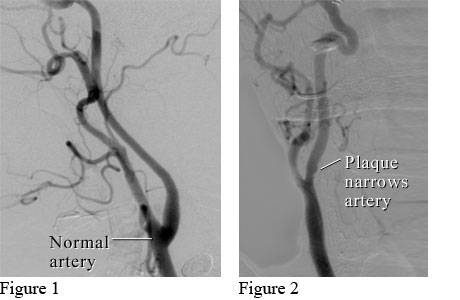

Here's what plaque buildup looks like in this angiogram of a carotid artery:

Plaque can form where arteries were damaged. Besides causing blockages, flakes of plaque can break away and travel to the brain. Or the plaque can rupture, allowing blood-cell fragments (platelets) to accumulate and possibly form blood clots.